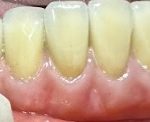

Cô U70 tình trạng vệ sinh răng miệng kém, quá nhiều cao răng gây tiêu xương, lung lay dẫn tới chỉ định nhổ các răng không thể giữ lại được ở hàm dưới và phục hồi lại bằng implant hàm dưới. Kế hoạch điều trị bao gồm vệ cao răng toàn bộ các răng hàm […]